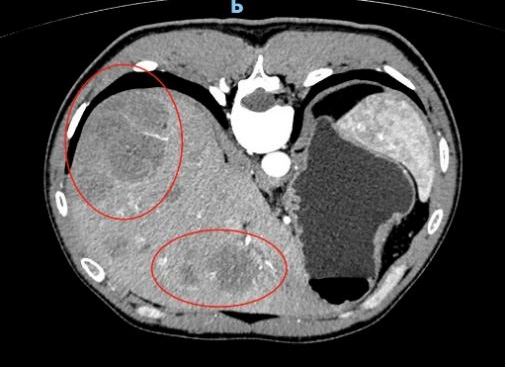

随后的病理结果提示,小秦确诊结直肠多发息肉病,其中多枚较大息肉已经进展为腺癌,且CT显示肝脏有异常结节,考虑癌细胞转移,已经到了晚期,仅切除肠道病变对生存意义不大。目前小秦在我院肿瘤科进行化疗,希望能将肿瘤缩小转化,创造手术机会。医护对此都感到很痛心。

(CT下显示肝脏转移)